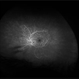

- peripheral ischemia

- Imaging device

- Fundus camera

- Peripheral ischemia by angiography with montage